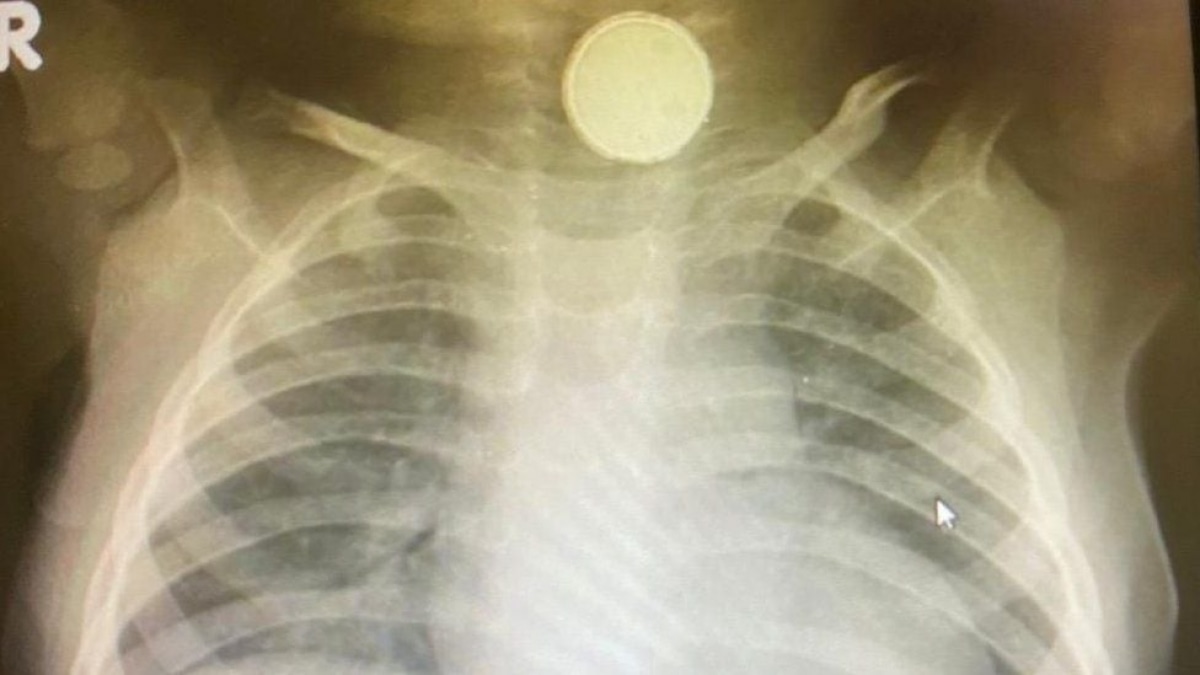

В англійському містечку Суіндон одинадцятимісячна дівчинка чотири місяці прожила з батарейкою у стравоході. Про це пише BBC

Медики вважали, що у дівчинки тонзиліт. У травні їй вирішили зробити рентгенівський знімок. Дослідження показало, що у стравоході дівчинки була батарейка розміром з велику монету. Поступово шлунковий сік її почав роз'їдати, що позначилося на здоров'ї доньки. Весь час Софія-Грейс відмовлялася від твердої їжі.

Лікарі провели дівчинці двогодинну операцію та видалили предмет. Хірург зазначив, що дитина вижила завдяки тому, що батарейка вже була стара та розряджена.